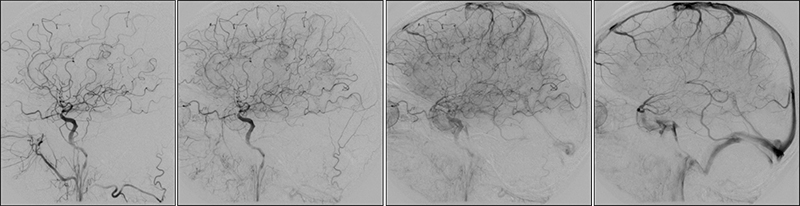

Εικόνα 3 και 4: Προσθιοπίσθια και πλάγια ενδοκράνια λήψη εγχύσεως στην αριστερή κοινή καρωτίδα. Υποτυπώδης ροή μόνο προς την αριστερή μέση εγκεφαλική (έμμεσο στοιχείο κινητοποιήσεως της παράπλευρης κυκλοφορίας από την αντίστοιχη πλευρά).

03

04

Εικόνα 5: Έγχυση στην δεξιά κοινή καρωτίδα. Εκτεταμένη αθηρωματική πλάκα του βολβού της δεξιάς έσω καρωτίδος, προκαλεί συγκεντρική στένωση 80-90%, χωρίς εξέλκωση.

05

Εικόνα 6: Προσθιοπίσθια ενδοκράνια λήψη εγχύσεως στην δεξιά κοινή καρωτίδα. Κίνητοποίηση της παράπλευρης κυκλοφορίας διά μέσου της προσθίας αναστομωτικής αρτηρίας με άρδρευση πλήρως της αριστερής πρόσθιας εγκεφαλικής και συμμετοχή στην άρδρευση της αριστερής μέσης εγκεφαλικής αρτηρίας.

06